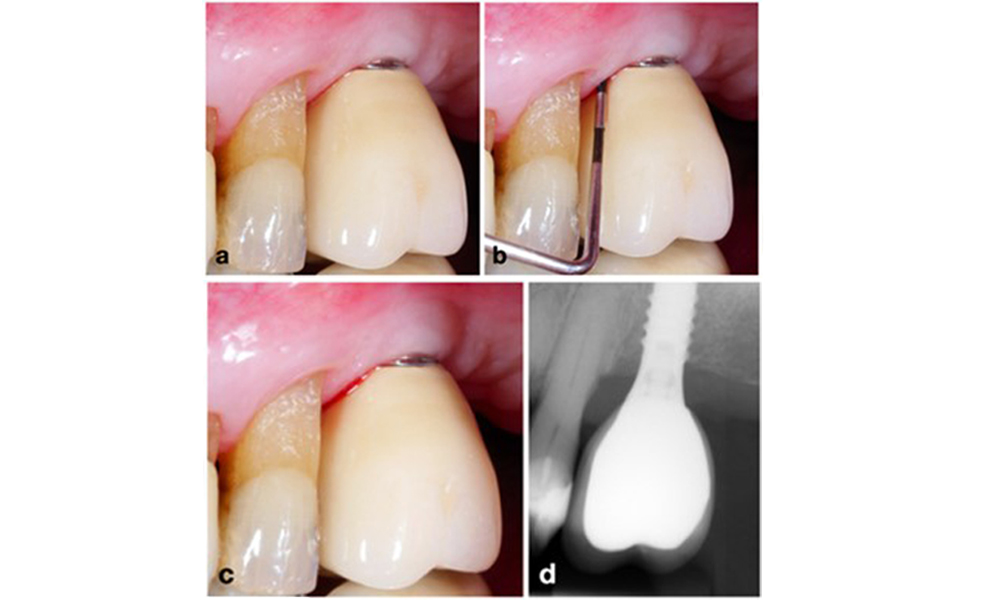

Le World Workshop on the Classification of Periodontal and Peri-Implant Diseases and Conditions de 2017 a établi des critères de diagnostic pour la mucosite péri-implantaire et la péri-implantite (Renvert et al. 2018). La mucosite péri-implantaire est définie comme (1) la présence d'une inflammation autour de l'implant (c'est-à-dire une rougeur, un gonflement, une ligne ou une goutte de saignement dans les 30 secondes suivant le sondage), associée à (2) l'absence de perte osseuse supplémentaire après la cicatrisation initiale (figure 1).